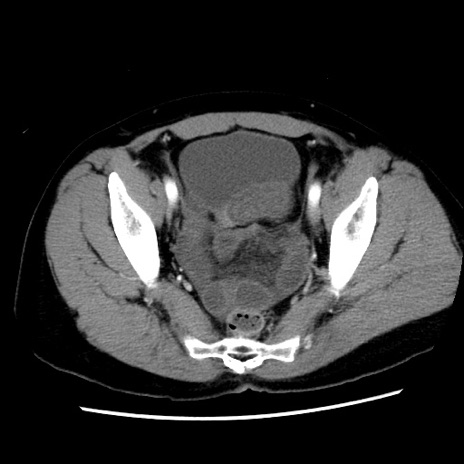

症例10(横断像)

【症例】 50歳代女性

【主訴】 腹痛

【現病歴】前日生レバーを食べた。今朝に排便あり。 昼前に突然発症の腹痛を生じ、当院救急外来を受診した。

【既往歴】 子宮筋腫にてで子宮全摘後

【身体所見】 意識清明、腹部:平坦、軟、下腹部やや左を中心に圧痛・反跳痛あり、筋性防御あり

【データ】WBC 7800、CRP 0.07